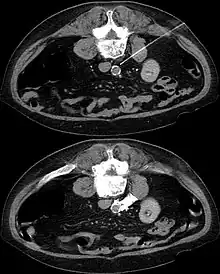

The sympathetic plexus can also be blocked in other parts of the body. Lying on the major abdominal vessels sympathetic plexus may, for example, under local anesthesia guided by a CT scan it can be turned off by injection of concentrated alcohol (interventional radiology).

In CT guided lumbar sympathicolysis, the site of neurolytic solution injection is chosen at the level of L2-L3 vertebra level. The needle should avoid the vertebral transverse process, ureter, pelvicalyceal system, and other major blood vessels. The target injection site would be anteromedial to the psoas muscle and dorsolateral to the abdominal aorta, where the sympathetic trunk would most likely be located.[1]

After the skin of the puncture site is cleaned, 2% lignocaine is injected into the to numb the skin and also the needle trajectory. Then a 22G China needle is inserted into the target site, which is bounded by the vertebral body, aorta, inferior vena cava, and psoas muscle. This region houses the lumbar sympathetic ganglion. Then, iodinated contrast medium (iohexol) and lignociane is injected into the target site to check the position of the needle tip. Once the needle tip position is confirmed, a mixture of neurolytic solution (99.9% alcohol) and iodinated contrast medium (at a ratio of 10:1) is injected into the target site.[1]